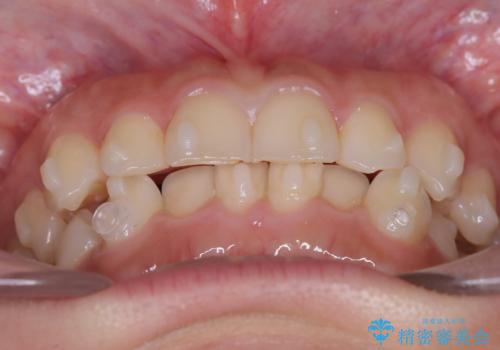

- 前歯のガタガタが気になるとのことでご相談いただきました。診察すると、歯列のスペースが不足し、前歯が重なっている状態でした。抜歯をせずに整えるため、歯と歯の間をわずかに削るIPR(歯列幅径削除)と、奥歯を後方へ動かす遠心移動を組み合わせてスペースを確保しながら並べる治療計画を立てました。

インビザラインを用いて歯を少しずつ移動させながら、IPRで微調整を行い、スペースを確保しました。また、奥歯を遠心移動させることで、前歯を自然な位置に並べることができました。治療後は、「ガタガタがなくなり、スムーズな歯並びになった」と患者様にもご満足いただきました。